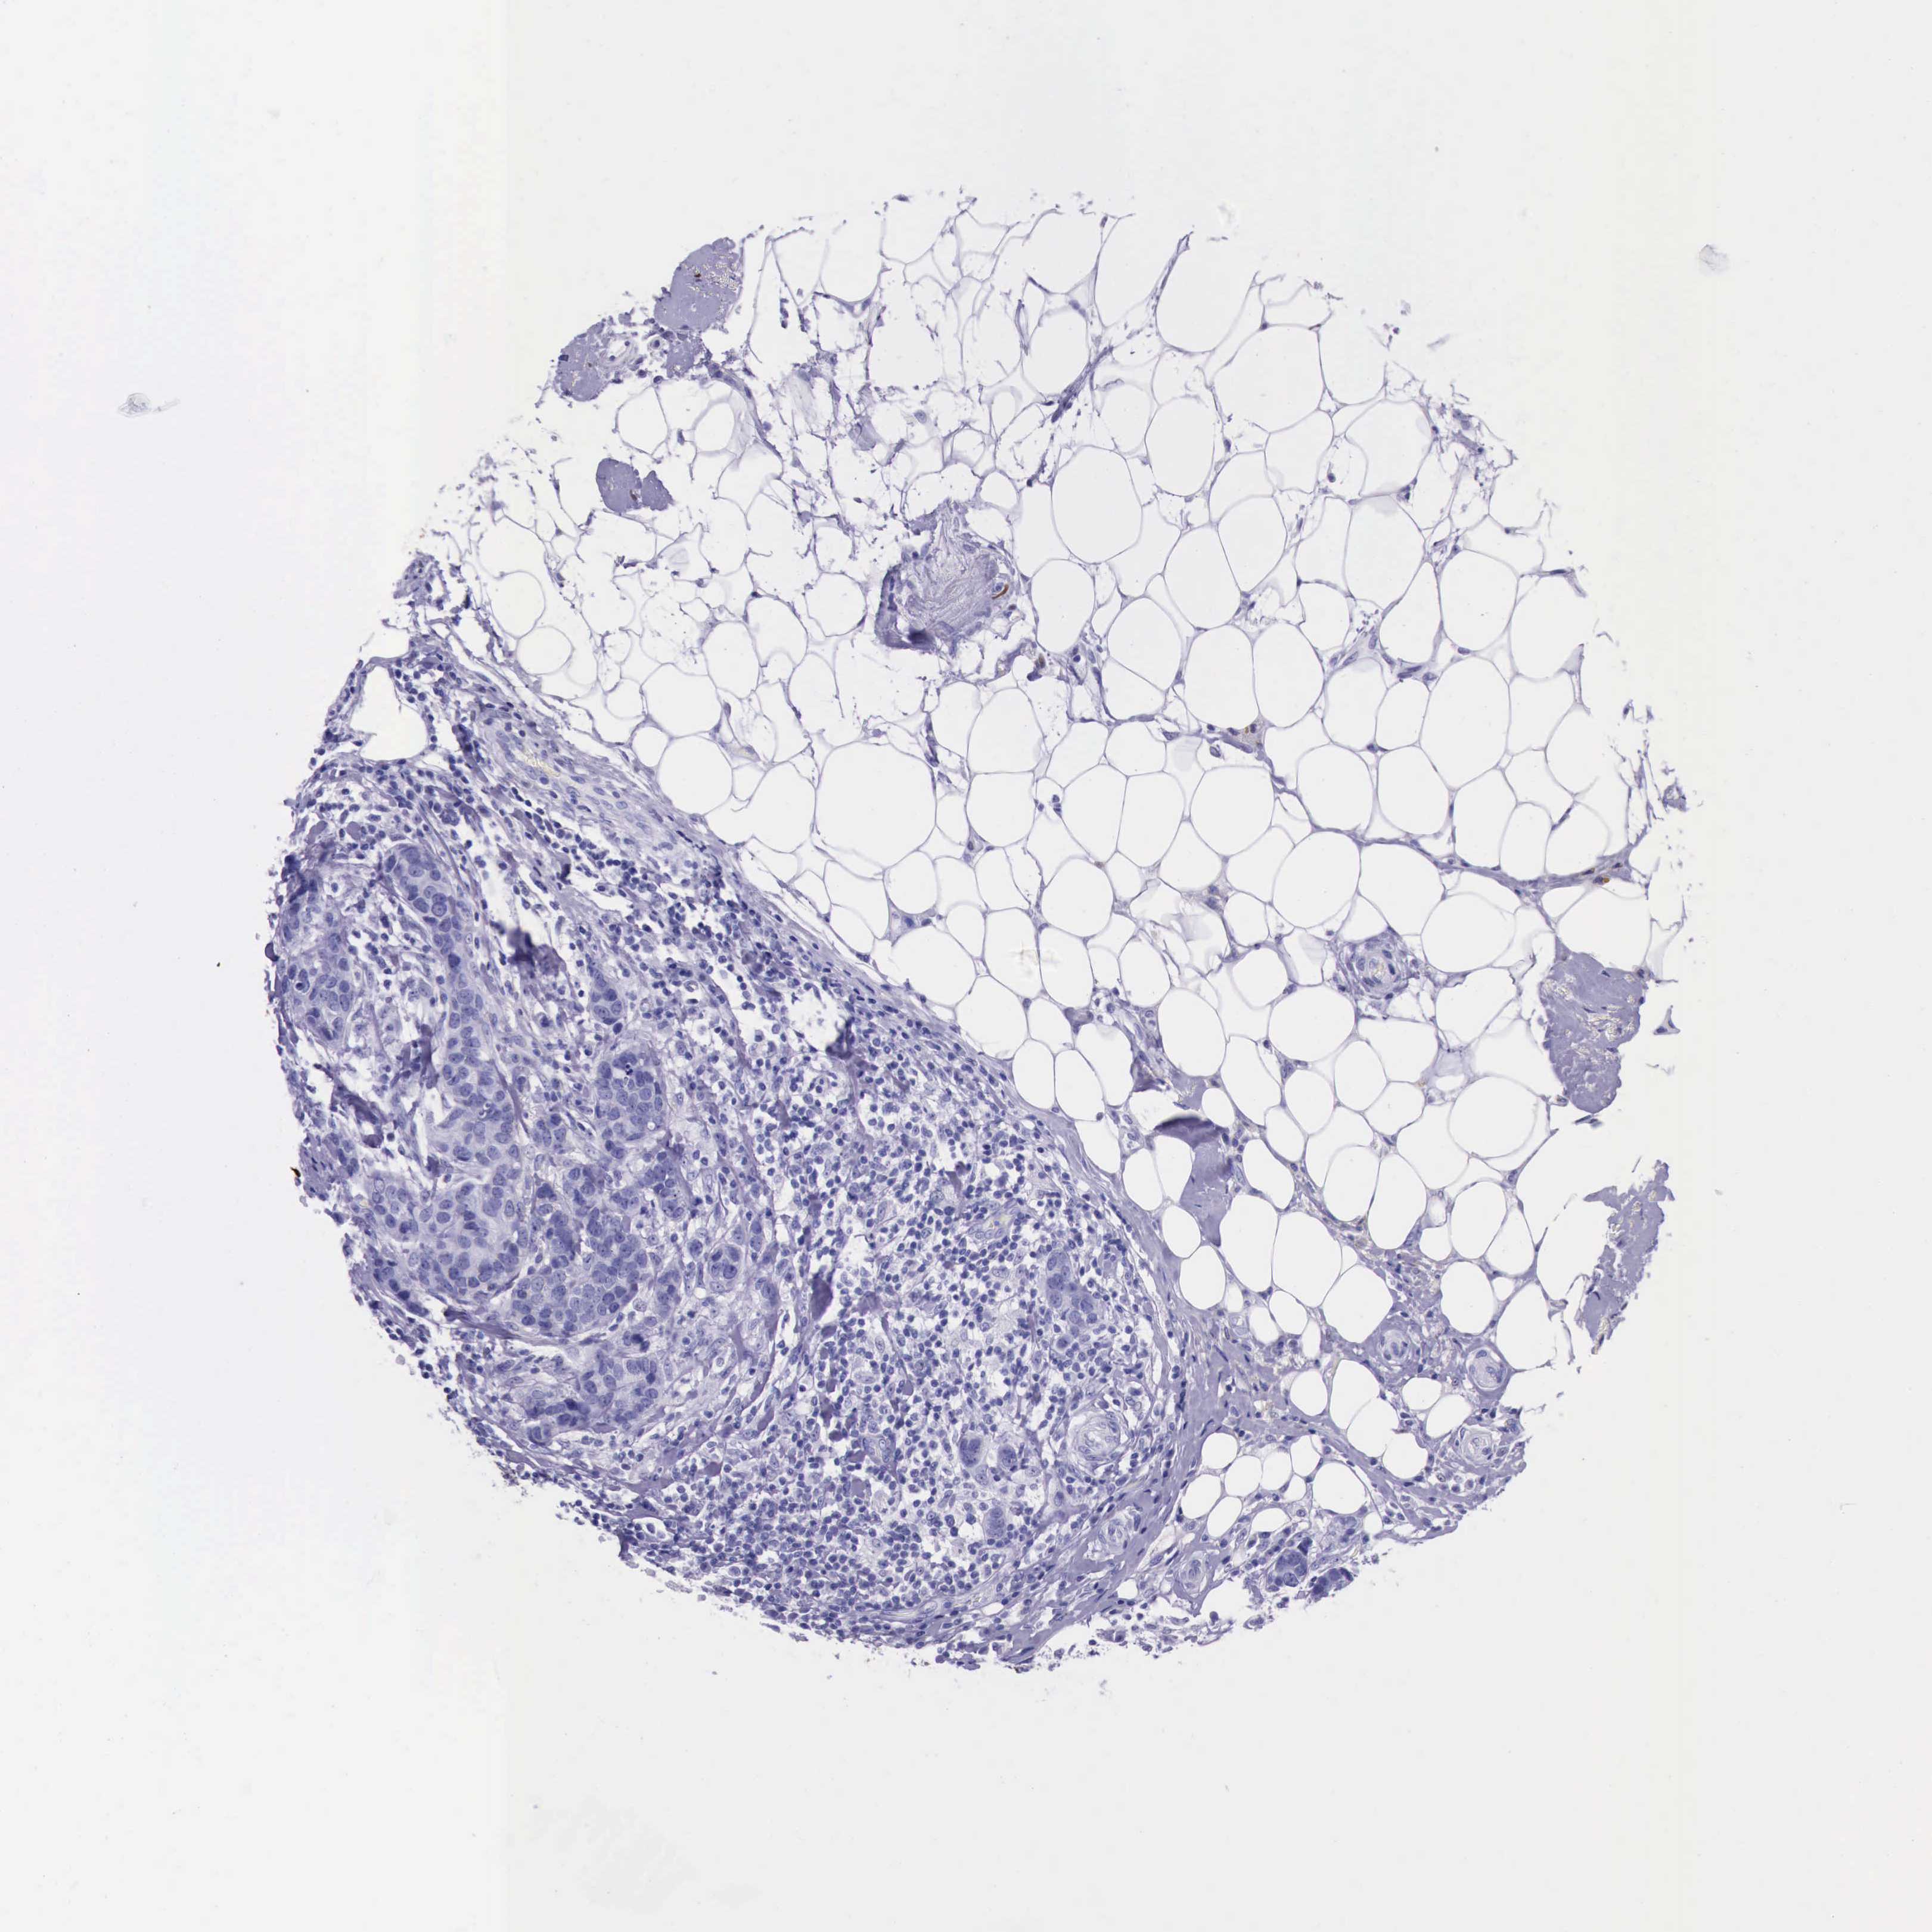

Breast cancer

Human cancer